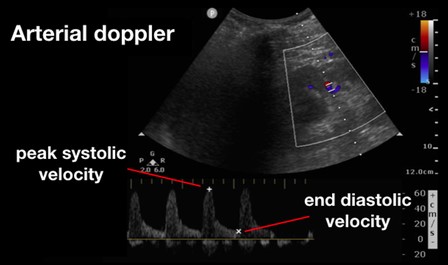

Figure 4. Renal Arterial Resistive Index (RI) 10

(Reproduced with permission from Rola, Spiegel, and Haycock)

Beyond the liver, the renal artery and vein play an important role in the assessment for venous congestion and fluid overload. To accomplish this, doppler evaluation typically aims to determine blood flow within the interlobular or arcuate vessels within the renal parenchyma. As both the artery and vein run together, the renal arterial and venous waveforms are usually obtained simultaneously. For the artery, a pulsatile waveform is located as seen in Figure 4. The renal resistive index (RRI) can then be calculated by taking the systolic peak velocity minus the end-diastolic velocity over the peak systolic velocity (RRI = [Vs-Vd]/Vs). When this value is greater than 0.7, it is considered to be pathologic, and is concerning for decreased renal perfusion via a decrease in diastolic arterial blood flow. As this value approaches 1, the diastolic arterial blood flow is absent. This finding, however, is nonspecific for venous congestion itself, although impairments in arterial flow can provide a window into venous congestion, especially within cardiac patients.